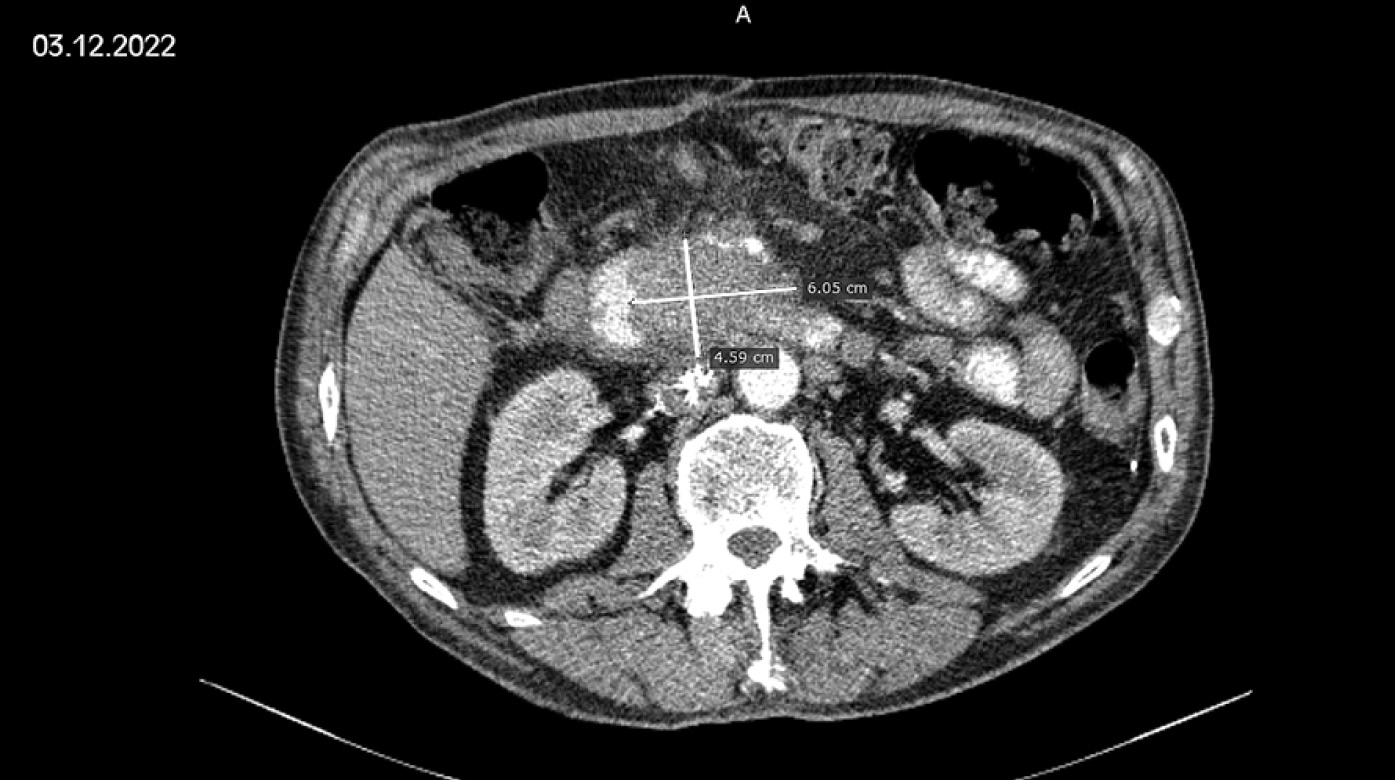

03.12.2022 г. — Компьютерная томография (КТ) показала увеличение образования головки поджелудочной железы (60,5×45,9 мм) на 37,5% по сравнению с проведённым ранее исследованием (05.07.2022 г.), установлена прогрессия заболевания (рис. 1).

Рис. 1. Компьютерная томография от 03.12.2022 г. (до начала цитокиногенетической терапии). Образование головки поджелудочной железы после 13 курсов полихимиотерапии по схеме FOLFIRINOX.

Fig. 1. Computed tomography from 03.12.2022 (before the start of cytokinogenetic therapy). Formation of the head of the pancreas after 13 courses of polychemotherapy according to the FOLFIRINOX regimen.

Окружающая образование парапанкреатическая клетчатка инфильтрирована; инфильтрация распространяется на область брыжейки тонкой кишки. Верхняя брыжеечная и гастродуоденальная артерии проходят в толще образования, сужены. Верхняя брыжеечная вена на фоне образования не прослеживается (вовлечена). Воротная вена прилежит к верхнему полюсу образования, граница между ними не прослеживается. Определяются увеличенные мезентериальные (21×9 мм), парааортальные (15×18 мм), межаортальные (16×17 мм) и паракавальные (16×18 мм) лимфатические узлы.

Заключение: опухоль головки поджелудочной железы с признаками распространения на окружающую клетчатку и вовлечения 12-перстной кишки, верхних брыжеечных артерии и вены; аэрохолия; забрюшинная лимфоаденопатия. По сравнению с исследованием от 05.07.2022 г. отмечается прогрессия заболевания, сумма наибольших/наименьших диаметров таргетных очагов (СНД) — 107,5 мм.